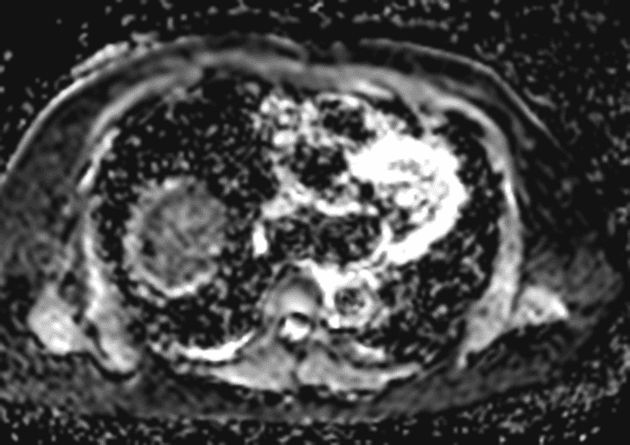

- Tổn thương dạng thùy (lobulated) kích thước 35 x 45 mm nằm ở phân đoạn V của thuỳ phải, liền kề với túi mật (gallbladder).

- Tổn thương này tăng tín hiệu (hyperintense) trên hình ảnh T2-weighted MRI.

- Trên hình ảnh cộng hưởng từ có tiêm thuốc tương phản động (dynamic contrast-enhanced imaging), thấy tăng quang dạng nốt (nodular) ở vùng ngoài viền (peripheral) ban đầu, tiếp theo là quá trình lấp đầy dần từ ngoài vào trong (slow centripetal filling).

Hình ảnh cộng hưởng từ (MRI) phù hợp điển hình với u sợi mạch gan (hepatic hemangioma).

U sợi mạch gan là khối u gan lành tính phổ biến nhất, thường được phát hiện tình cờ trên hình ảnh học. Bệnh xuất phát từ các mạch máu bất thường và gồm các khoang giãn chứa đầy máu được lót bởi tế bào nội mô. Trên cộng hưởng từ (MRI), hình ảnh điển hình bao gồm tăng tín hiệu rõ rệt trên T2 và kiểu tăng quang dạng nốt ở vùng ngoại vi trong thì động mạch, tiếp theo là quá trình lấp đầy dần từ ngoài vào trong ở các thì muộn. Dấu ấn hình ảnh này rất đặc hiệu, cho phép chẩn đoán chắc chắn không xâm lấn trong hầu hết các trường hợp. Mặc dù có thể sinh thiết, nhưng thủ thuật này tiềm ẩn nguy cơ chảy máu và thường được tránh. Điều trị mang tính bảo tồn, không cần cắt bỏ hay theo dõi định kỳ trong các trường hợp điển hình, trừ khi có nghi ngờ chẩn đoán hoặc bệnh nhân có triệu chứng.